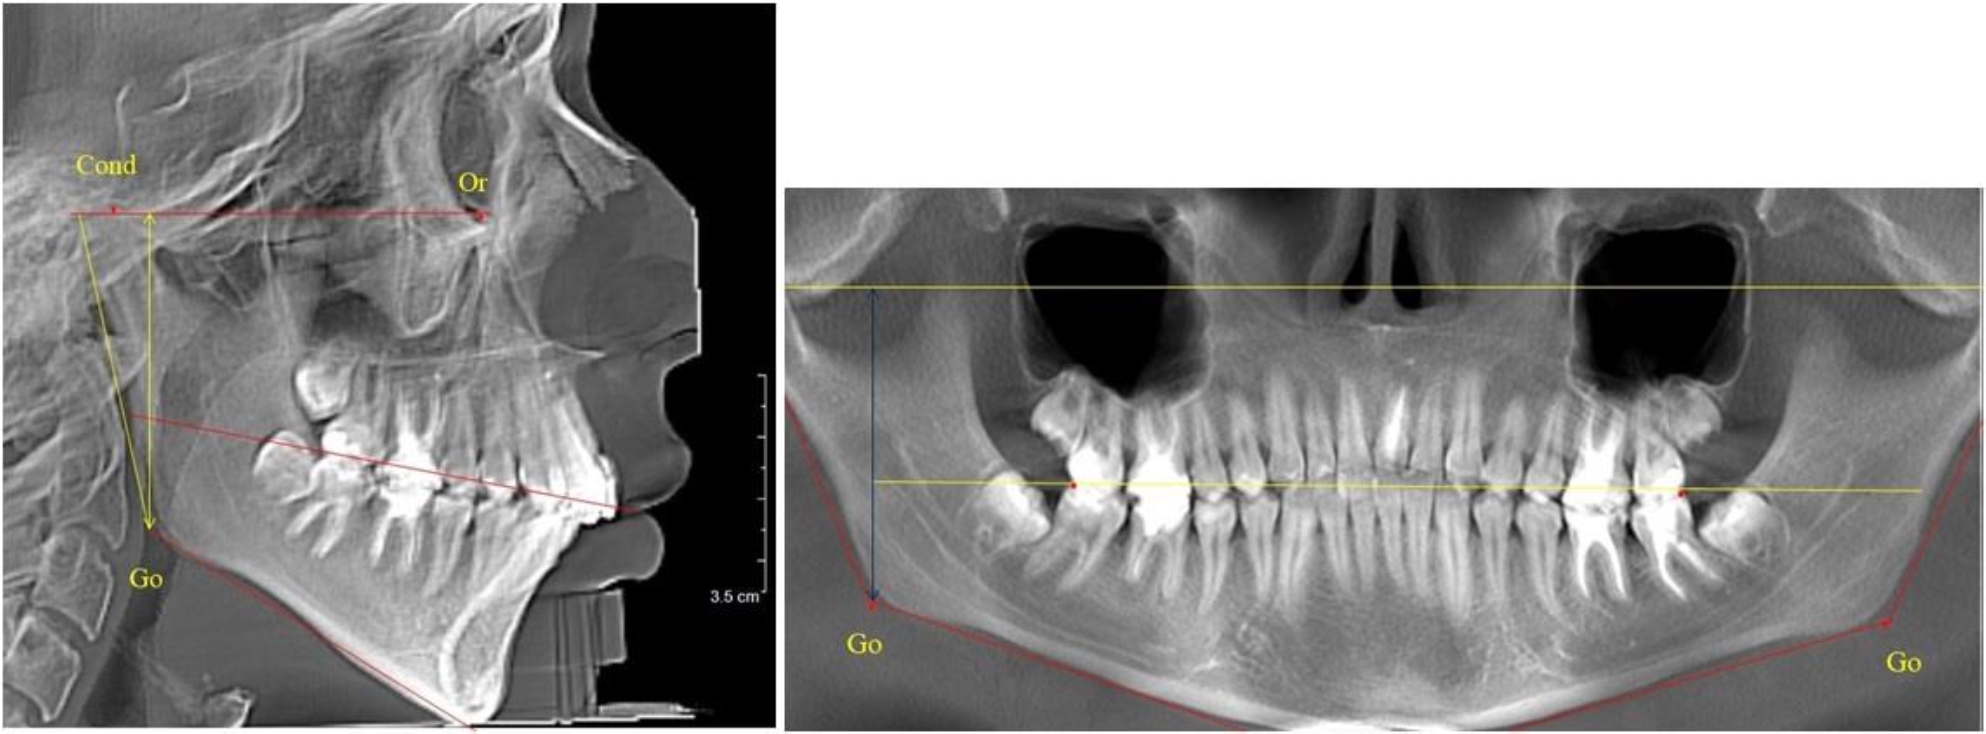

В 3-й группе были проанализированы 9 телерентгенограмм и 9 ортопантомограмм, что составило (8,49 ± 2,71) % от числа изученных рентгенограмм (рис. 3).

Рис. 3. ТРГ и ОПТГ пациента после смены молочных резцов

На всех рентгенограммах произошла смена молочных резцов постоянными. Окклюзионная линия делила ветвь на два отдела.

Высота ветви у детей у детей 3-й группы составляла (51,07 ± 2,72) мм, что было достоверно больше, чем у детей 1-й группы (р ˂ 0,05). При этом высота верхней окклюзионно-суставной части была (29,06 ± 1,44) мм, а нижней – (22,01 ± 1,59) мм. Высота верхней части была больше нижней, что и определяло особенности соразмерности частей ветви нижней челюсти в анализируемый возрастной период.

Относительные показатели соразмерности частей ветви нижней челюсти показали, что отношение высоты верхней части ветви к нижней в среднем составляло 1,32 ± 0,14. Отношение общей высоты ветви к верхней ее части составляло 1,75 ± 0,12, а отношение общей высоты ветви к нижней ее части было 2,32 ± 0,17, что и определяло особенности соразмерности частей ветви нижней челюсти в анализируемый возрастной период.